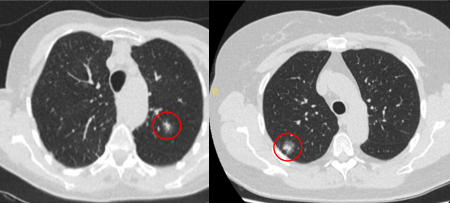

Semi-solid nodules: growth of the solid component suggests that further investigation and/or treatment should be considered.[Figure caption and citation for the preceding image starts]: Computed tomography (CT) sections with examples of semi-solid solitary nodulesFrom the collection of Dr George Tsaknis, MD, PhD, FRCP(London), MRQA, MAcadMEd, PGCert; used with permission [Citation ends].